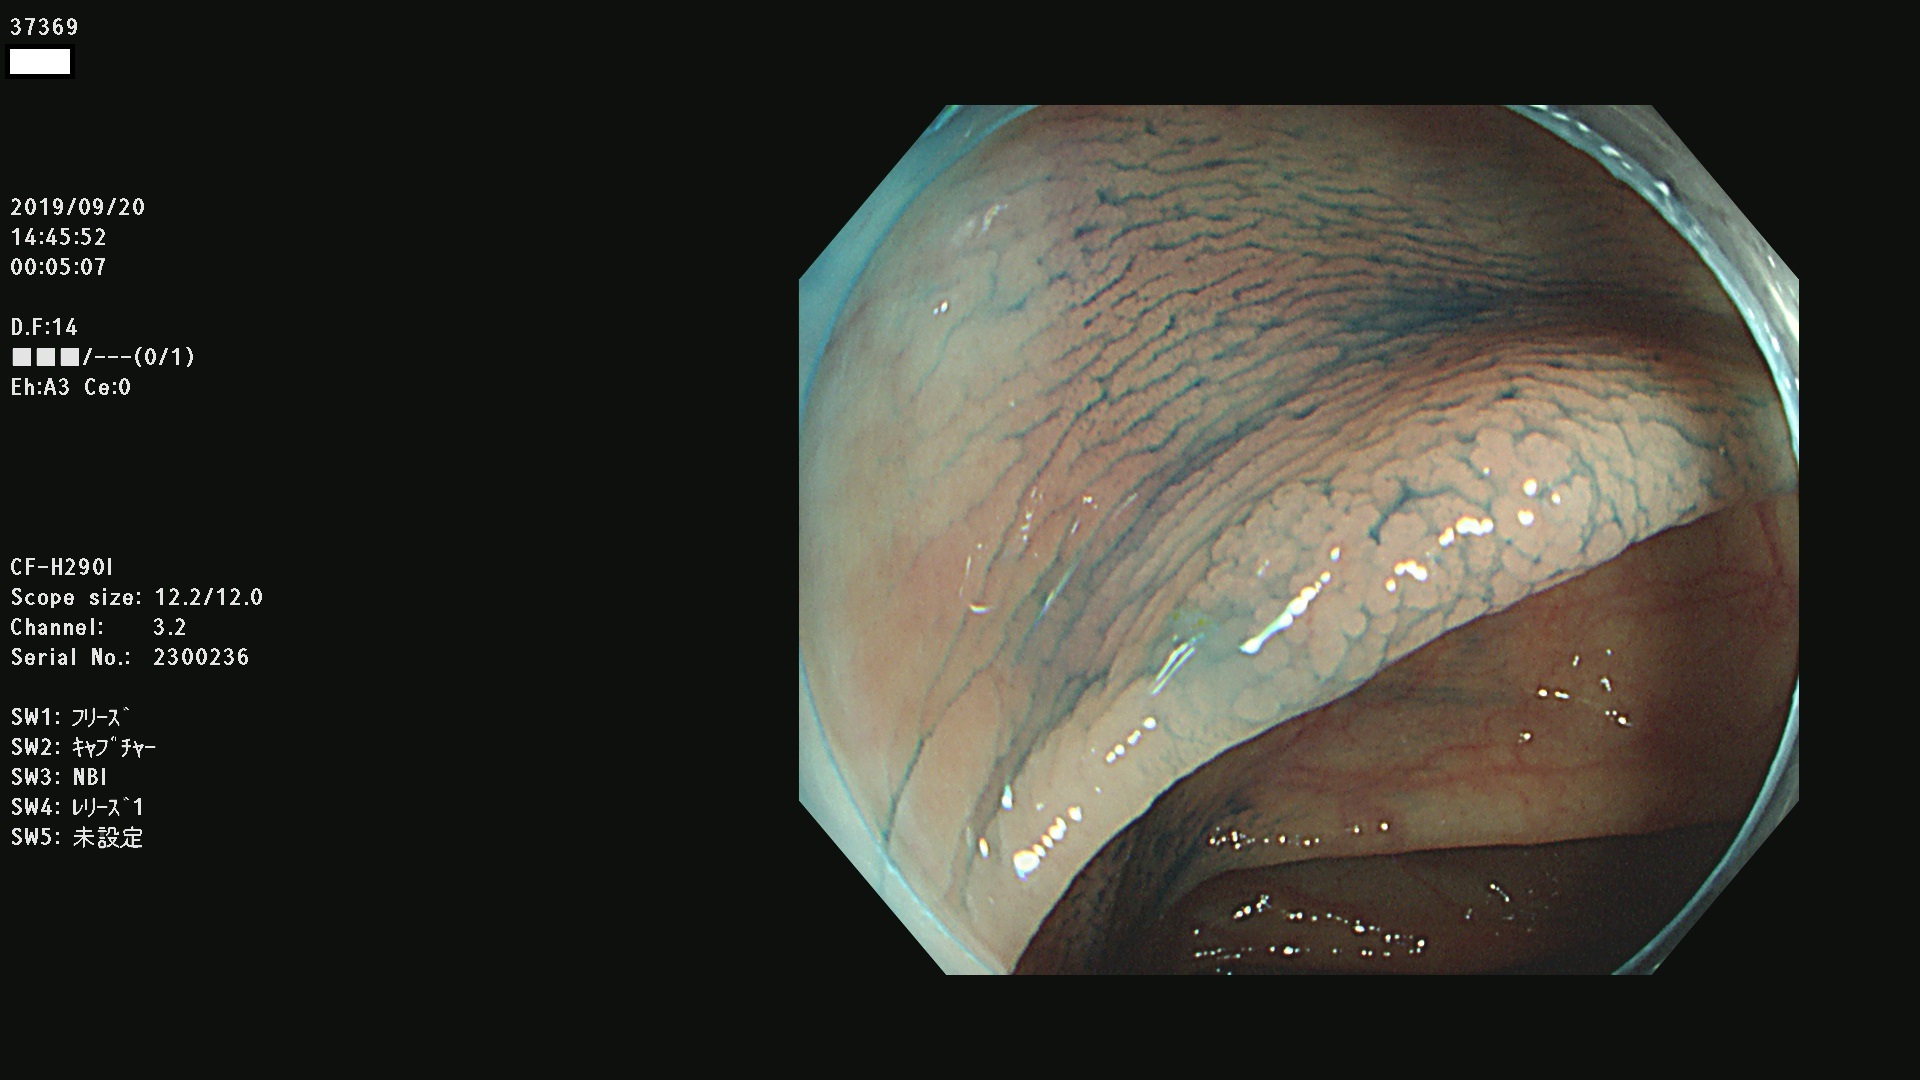

37300(SSAPのみ) 37301 37303 37304 37306 37307 37308 37309 37312 37313 37315(SSAPのみ) 37316 37317(SSAPのみ) 37319 37321(SSAPのみ) 37322 37323 37324 37325 37326 37328(SSAPのみ) 37329 37330 37331 37332(SSAPのみ) 37333 37334 37336 37337 37338 37340 37342 37343(SSAPのみ) 37344 37345 37346 37347 37348 37352(SSAPのみ) 37353 37354 37355 37356 37358 37360 37361(SSAPのみ) 37362 37363 37366 37367 37369 37370 37371 37372(SSAPのみ) 37375 37376 37377 37380 37381(SSAPのみ) 37382 37383 37384 37385(SSAPのみ) 37386 37387 37388 37389 37390 37392(SSAPのみ) 37393 37394 37395 37396(SSAPのみ) 37397 37398(SSAPのみ) 37399

発見困難で危険性の高い平坦型病変(上記100名より抽出) )